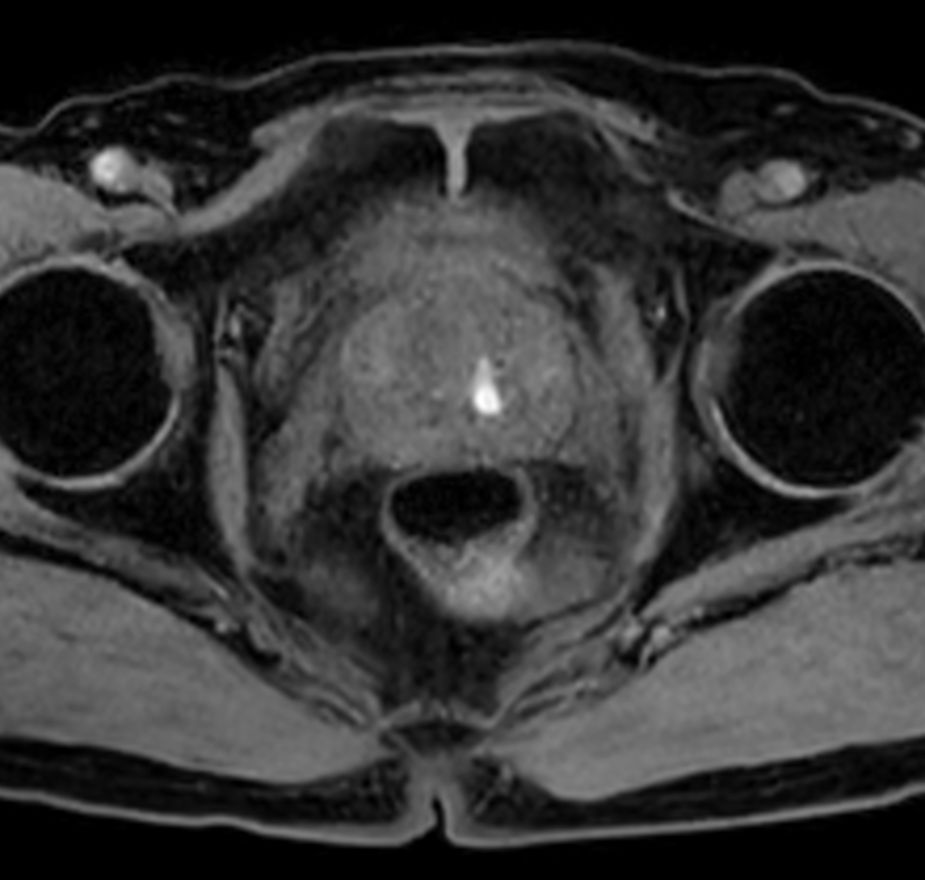

T1w TSE - Compressed SENSE